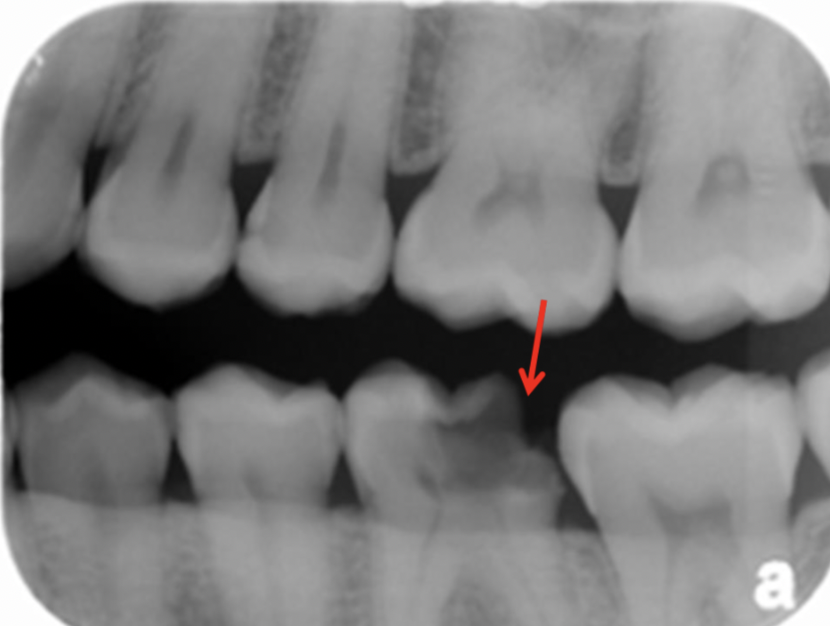

Q

Classify the caries

A

initial caries (IC)